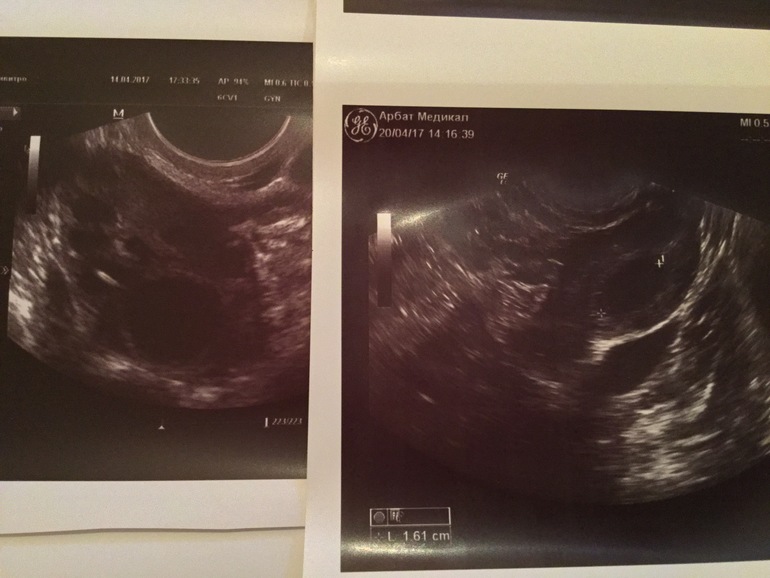

Но мучают сомненья может быть это ЖТ ! Уже было)) Слева фото ЛЯ от 14. 04 справа от 20.04 оба по замерам 16мм. Но блин справа на Жт смахивает и кровообращение повышеное было и снизу темное это сосуд кровеносный надутый которого на 1м узи небыло?Эндик паршивый не спорю((